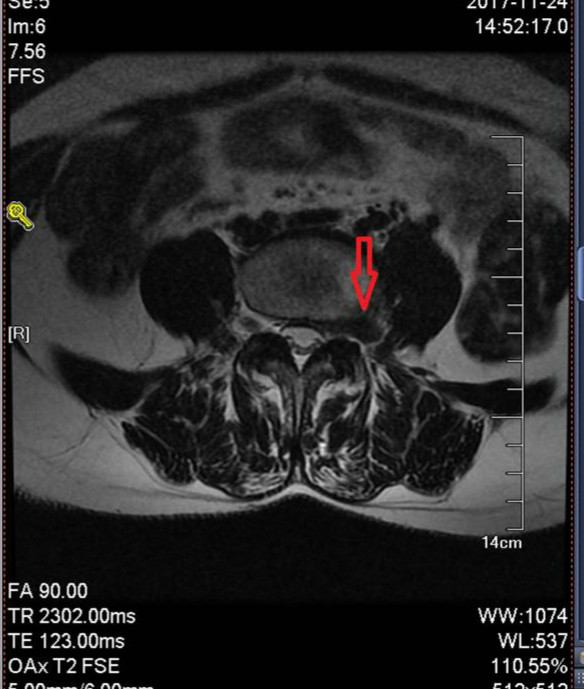

极外侧腰椎间盘突出:指突出物不位于椎管内,而是位于椎间孔或椎间孔外侧的特殊类型腰椎间盘突出,压迫该节段出口神经根引发症状,发病率占腰椎间盘突出的9%-10%左右,好发于L4/5节段,临床易漏诊误诊。

图中的C型就是极外侧间盘突出,没有经验的骨科医生这种情况是很容易漏诊的。下面用一个具体病例来说明这种特殊情况。

56岁的张阿姨(化名)腰腿疼病史好几年了,一直没查出来原因,先后去了大大小小的医院看过病,都告知腰肌劳损,回家养一养就好了,这一养就是好几年,症状没好转,反而最近1个月明显加重了,已经到了走路发瘸的地步,每天靠吃止疼药度日,后来在听病友说我们医院治疗腰腿疼效果好就来我们医院看病,经过查体,我们高度怀疑腰椎间盘突出,给患者做了个腰椎磁共振果然发现了元凶,就是这种极外侧的特殊类型腰脱